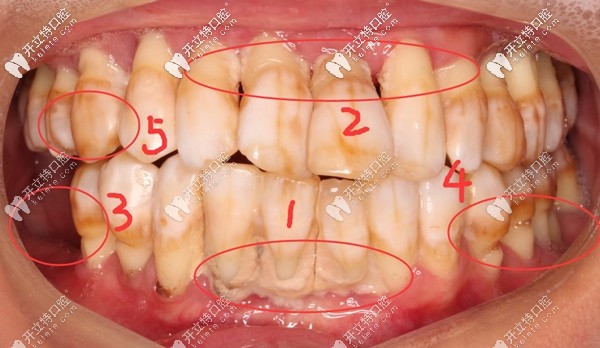

其實(shí)鄧?yán)蠋煹臐M(mǎn)口牙齒基本都在,但,一顆都留不住,因?yàn)槿慷紦u搖欲墜,牙根只有很淺一截在牙槽骨內(nèi),失去了咀嚼功能。

牙齒問(wèn)題:①牙結(jié)石沉積 ;②重度牙周炎引起牙齦萎縮,牙根暴露;③牙齒楔形缺損;④四環(huán)素牙;⑤牙齒晚上痛到影響睡覺(jué),痛的程度感覺(jué)已經(jīng)無(wú)法忍受了;⑥輕輕咬一點(diǎn)東西牙齒都在里面動(dòng)....